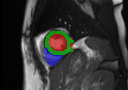

Multi-view segmentation.

The competence of our model to perform end-to-end segmentation across all planes is shown in Table 2 and Fig. 3. Our model not only exhibits comparable quantitative dice scores with nnUNet (that leverages exhaustive parameters tuning) but also shows superior performance over UNETR+ in all regions for both SA/LA planes. This benefit is gained from the learned whole-heart representation. Moreover, the superior performance against SA-only and LA-only segmentation also highlights the significance of integrating multi-view CMR information for more accurate segmentation outcomes.

GTnnUNetUNETR+Ours SA/LA onlyOurs AllRefer to captionRefer to captionRefer to captionRefer to captionRefer to captionRefer to captionRefer to captionRefer to captionRefer to captionRefer to captionRefer to captionRefer to captionRefer to captionRefer to captionRefer to caption

Figure 3: Qualitative segmentation results among nnUNet, UNETR+, and the proposed methods. UNETR+ and the proposed approach in the last column (Ours All) use all sparse CMR sequences as network input, while nnUNet and the second last column (Ours SA/LA) are trained solely with either SA or LA views.